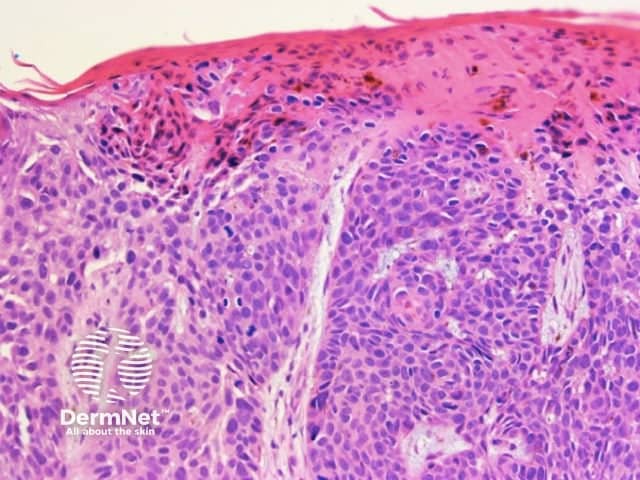

Regularly distributed circumferential pseudopods suggests a pigmented spindle cell (Reed) naevus whereas segmental pseudopods create asymmetry and are a clue to melanoma. In both cases, the histologic correlate is large nests of pigmented melanocytes at the periphery of the lesion (Figure 60).

Pseudopods are structures that resemble radial lines but that have a bulbous outer end. They only occur in combination with other patterns with the typical arrangement being pseudopods at the periphery and the other pattern centrally. The second pattern is most often structureless, with clods next in frequency, and reticular lines least common.